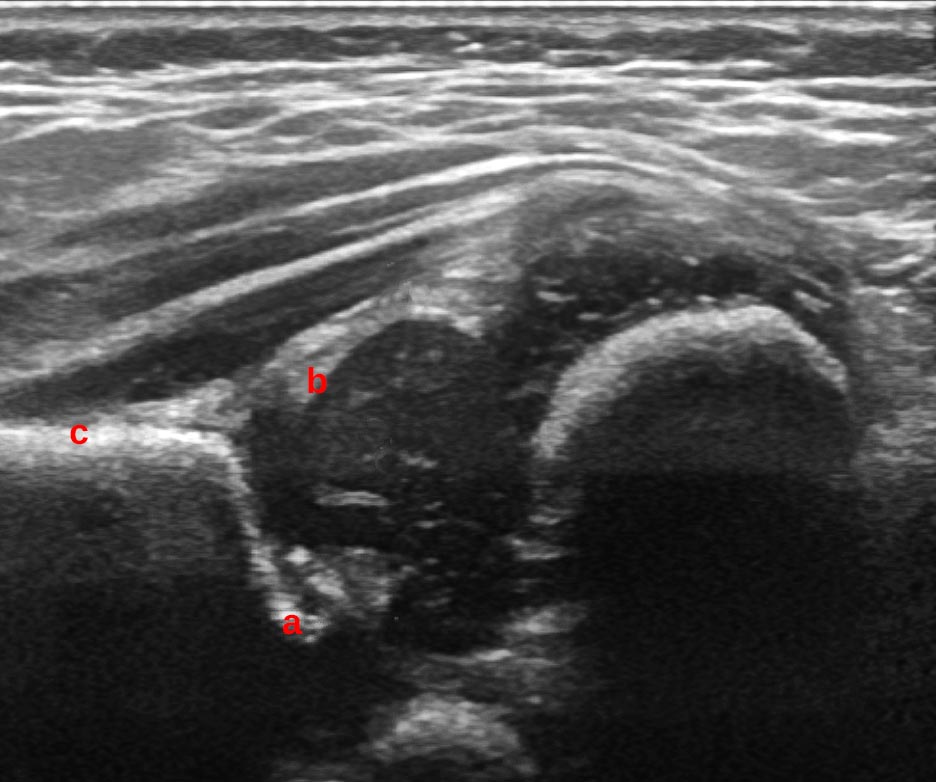

To measure the angle, a baseline plane is drawn along horizontal or vertical ilium starting at the point the perichondrium meets the ilium. A further line is drawn through points placed at the lower limb of the ilium and at the turning point. just touching the bone, not cutting in to it. The angle between baseline and this line is the alpha angle. The angle from the baseline to a line through the turning point and the middle of the labrum is the beta angle. The lines should not cross at a single point.

1. The chondro-osseous border

2. Femoral head

3. Synovial fold

4. Joint capsule

5. Labrum

6. Cartilage

7. Bony roof

8. Turning point - the point where the bony roof turns from convexity to concavity